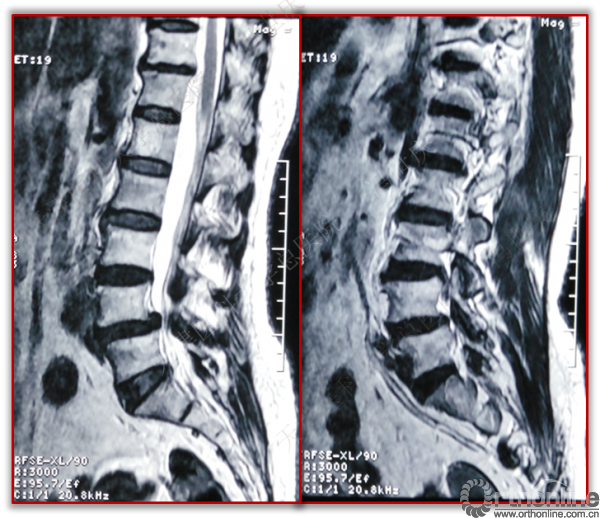

术前

术后